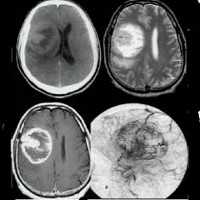

(а) На рисунке аксиального среза изображено объемное образование гетерогенной структуры с кистозным и солидным компонентами, распространяющееся на кору головного мозга и субкортикальное белое вещество, что типично для олигодендроглиомы. Обратите внимание на глубокую инфильтрацию мозговой ткани опухолью на их границе, а также ремоделирование кости свода черепа.

(б) Бесконтрастная КТ, аксиальный срез: у мужчины 20 лет в левой лобной доле определяется крупное кальцифицированное объемное образование - типичная олигодендроглиома. 70-90% олигодендроглиом характеризуются кальцификацией. Кальцификация таких опухолей помогает отличить эту опухоль от других глиом, в частности, от астроцитомы.

(а) Микропрепарат под высоким увеличением: определяется классический патогистологический симптом «яичницы», обусловленный перинуклеарным гало, что характерно для олигодендроглиом. Олигодендроглиомы характеризуются более благоприятным прогнозом, чем астроцитомы той же степени злокачественности.

(б) МРТ, постконтрастное Т1-ВИ, аксиальный срез: определяется гетерогенное контрастирование объемного образования в задней черепной ямке с вовлечением IV желудочка. Несмотря на то, что визуализационные признаки имитируют эпендимому, при резекции данная опухоль оказалась олигодендроглиомой grade II.